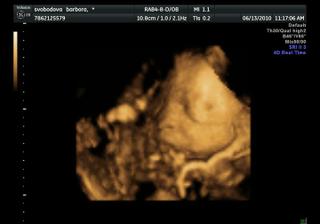

Náše bábetko a pupík🙂

Po 4 a půl letech jsme se rozhodli, že je nejvyšší čas pořídit si ten nejkrásnější dáreček 🙂 Po dvou snaženíčkách na nás vykoukly vytoužené //.